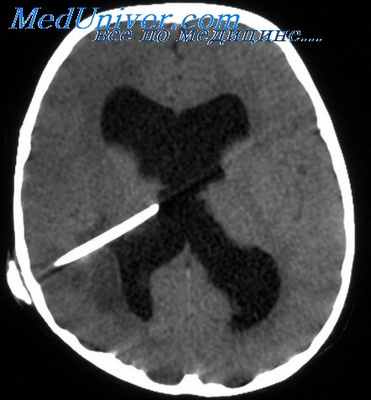

Супра- или инфратенториальные объемные образования в головном мозге могут быть причиной смещения (дислокации) как прилегающих, так и удаленных участков мозга. При односторонних супратенториальных образованиях, например опухоли, гематоме или абсцессе, постепенно происходит смешение структур головного мозга в противоположную сторону. Это обычно легко определить при нейровизуализации по боковому смещению срединных структур мозга, Таких как обызвествленное шишковидное тело или прозрачная перегородка. Значительная степень смешения срединных структур обычно сопряжена с угнетением сознания.

Смещение шишковидной железы на 3—5 мм. как правило, сопровождается состоянием сомноленции, смешение на 5—8 мм — сопором, смешение свыше 8 мм характерно для комы. По мере нарастания масс-эффекта происходит смешение в противоположную сторону поясной извилины с вклинением под мозговой серп, а медиобазальные части височной доли смещаются медиально и вниз, вклиниваясь под мозжечковый намет. Крючок (uncus) гиппокампальной извилины вклинивается между мозжечковым наметом и стволом мозга, что вызывает сдавление в узкой вырезке намета мозжечка как самого крючка, так и ствола мозга и глазодвигательного нерва (латеральное, или ункальное, транстенториальное вшипение).